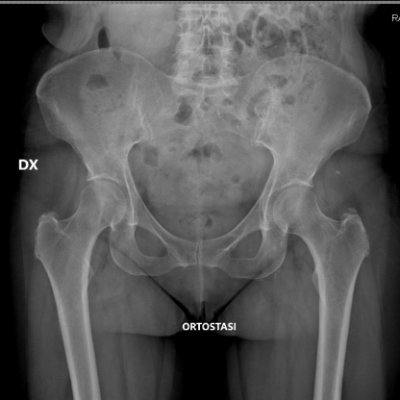

◣ le mie creste iliache nella pic ★ Twitter è l'evidenziatore giallo fosforescente ma senza gomma nulla cambia